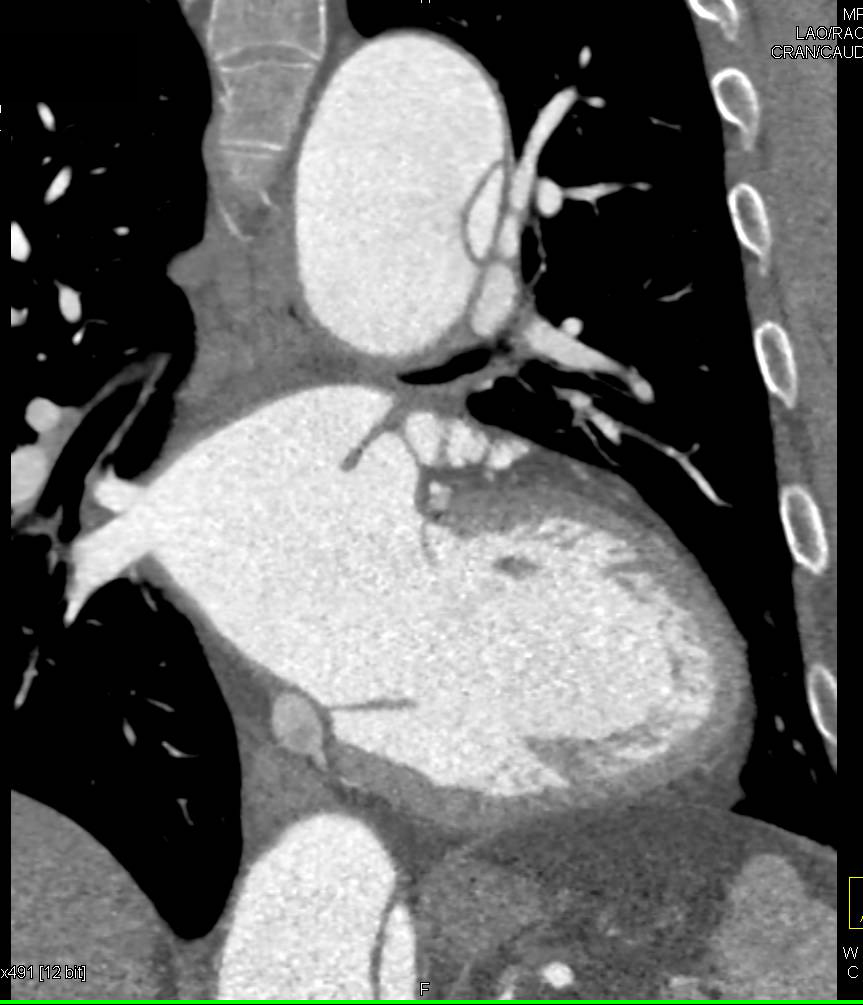

CCTA: Extensive Calcified Left Anterior Descending Coronary Artery (LAD)